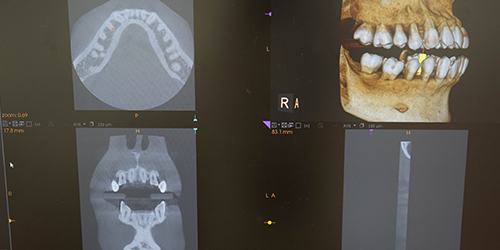

口全体を撮影できるデジタルレントゲンです。大まかな歯の状態や顎の骨の異常、歯の神経の位置などを知ることができ、歯周病や親知らずの抜歯などの診断をくだすのに欠かせません。